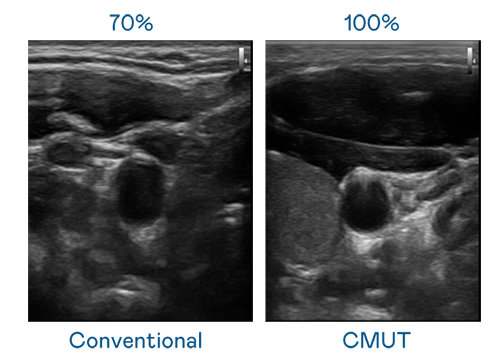

CMUT 技术是一种用电容式微机电元件来产生超音波讯号的技术。与传统 PZT 压电式技术相比,CMUT 频宽增加 30%,更宽频的超音波讯号让影像解析度大幅提升,是实现高影像品质医疗超音波扫描、促进精准医疗发展的关键技术。

超音波影像的解析度高低,首先取决于探头能发出的讯号频宽。云鼎国际 CMUT 可提供高清晰的超音波讯号,提供高频宽、高灵敏度、影像纹理细节更高的超音波影像,协助医护人员缩短影像判读时间及利用精准的医疗影像进行诊断。